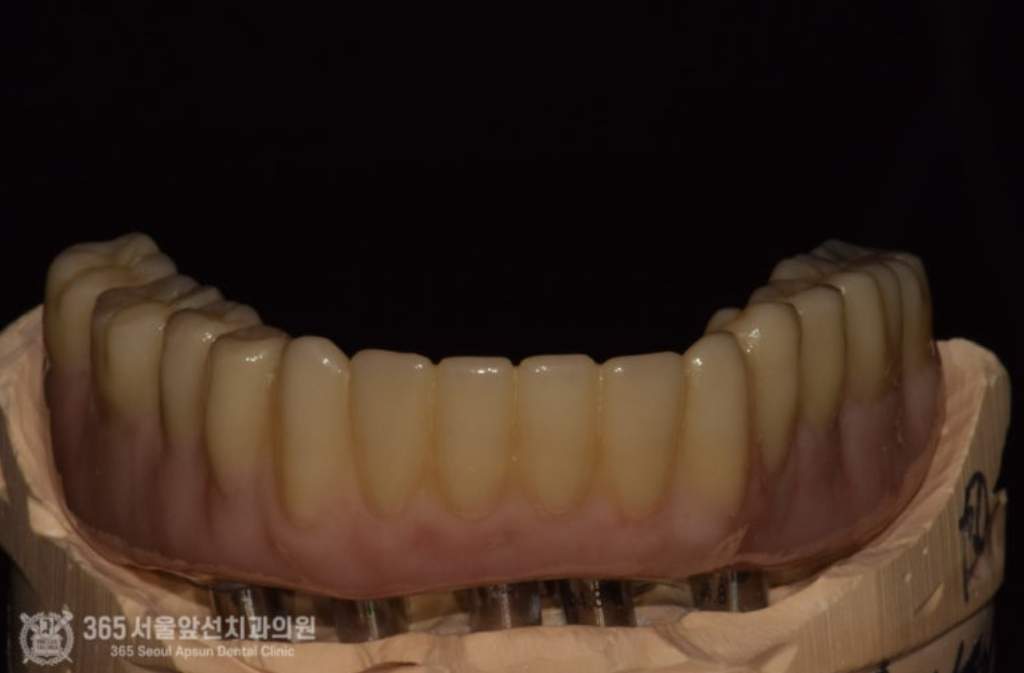

아래쪽에 임플란트 틀니를 썼었는데, 전체 임플란트 치료를 받고 싶어서 치과에 갔더니 뼈가 없어서 임플란트가 불가능하다고 판정받았어요. 촬영일시 : 2024.07.07. 처음 내원 당시 엑스레이 사진입니다. 촬영일시 : 2024.07.07. 사진에 노란색 표시를 한 곳이 신경관입니다. 보다시피 어금니 부위에는 뼈가 하나도 없습니다. 이 정도 뼈 상태라면 1000명의 환자분이 오신다면 그 중 단연코 1등으로 뼈가 안좋으신 상태 정도 됩니다. 기존의 임플란트는 제거를 해야하고, 이후 신경관을 피해서 5개의 임플란트를 식립하기로 했습니다. 촬영일시 : 2024.07.07. 수술 전 CT 사진으로 신경 구조물에 대한 정확한 사전 파악 후 수술에 들어갑니다. 왼쪽 아래턱 부위의 신경이 손상되지 않게 조심스럽게 수술을 진행했습니다. 오른쪽 아래턱 부위도 동일하게 신경이 손상되지 않게 조심스럽게 수술을 진행합니다. 기존 임플란트는 상태가 좋지 않아서 제거했습니다. 촬영일시 : 2024.07.07. 촬영일시 : 2024.11.16. 임플란트 수술 후 엑스레이입니다. 원하는 위치에 정확히 임플란트가 식립되었습니다. 임플란트가 뼈와 단단하게 굳으면 본을 떠줍니다. 정교한 보철물을 위해선 정확한 본뜨기 작업은 필수겠죠? 촬영일시 : 2024.11.16. 완성된 보철물입니다. 촬영일시 : 2024.11.16. 대략 4개월에 걸쳐 치료를 완료해드렸습니다. 환자분께서는 아주 만족하셨습니다. 정확한 임플란트 수술을 통해 신경 손상없이 성공적으로 마무리할 수 있었습니다 ㅎㅎ 촬영일시 : 2024.07.07. / 2024.11.16. 보철물 장착 전후의 입술 모습의 변화를 볼 수 있습니다. 입술이 볼록하게 지지받아서 자연스러운 안모로 변화했습니다. 촬영일시 : 2024.07.07. / 2024.11.16. 전후 구강내 사진입니다. 잇몸뼈가 많이 없으셔서 잇몸 부위를 핑크색이 나는 재질로 채워드렸습니다. 임플란트 불가능 판정을 받으셨던 환자분이신데 치료가 잘 마무리 되어 뿌듯했습니다 ㅎㅎ 신경관이 근접한 고난이도 임플란트 치료지만 충분한 경험과 지식이 있다면 치료가 가능하니 걱정 안하셔도 되겠습니다. 지금까지 365일 열린 가까운 서울대학교 치과병원을 지향하는 365서울앞선치과였습니다. 감사합니다. [ 치료기간 : 2024년 7월7일 ~ 2024년 11월 16일 ] ※ 365서울앞선치과의원의 모든 포스팅은 각 진료과 의료진이 직접 작성합니다. 365서울앞선치과의원 블로그의 임상 케이스 게시물은 환자분께 의학적으로 정확하고 상세한 정보를 드리기 위해 각 진료과 의료진이 직접 작성하며, 모든 증례 사진은 본원 의료진이 직접 시술한 증례를 촬영한 것으로, 의료법 제23조, 제56조에 의거하며 환자분의 동의를 얻어 포스팅에 사용하였습니다. 또한 해당 케이스는 본 환자분의 치료 결과이며, 환자 상태에 따라 치료의 결과는 달라질 수 있습니다. |